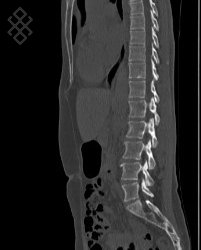

Scanner Corps Entier

Déroulement

La durée moyenne de l'examen est de 20 min.